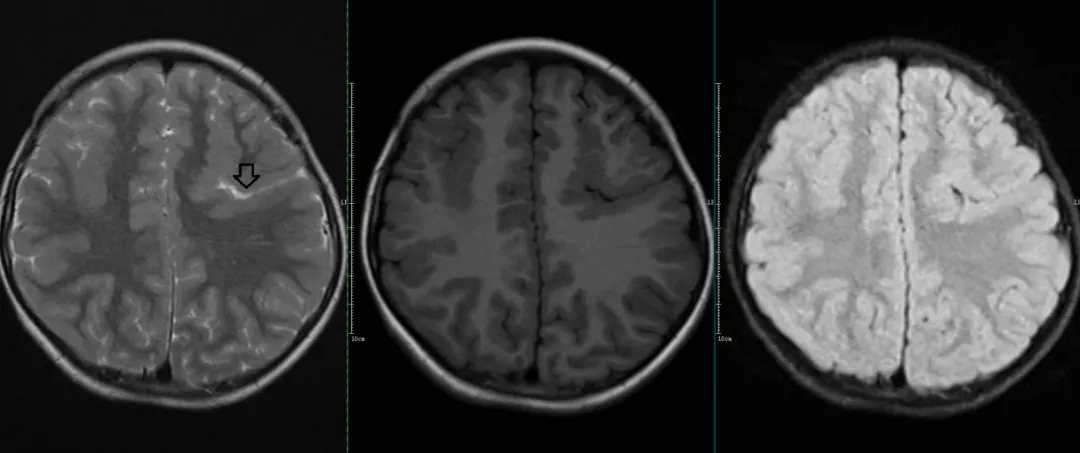

CASE1

左侧脑裂畸形伴灰质异位。

①室管膜下灰质异位:又称脑室周围灰质异位。这类最常见。MRI表现为沿一侧或两侧脑室旁分布的结节状灰质团块,单发或多发,其长轴与侧脑室壁平行,无水肿及占位效应,与正常灰质信号相似。

②皮质下局灶型灰质异位:较室管膜下型少见,MRI表现为异位的灰质团块位于正常的脑皮质下方,外观呈岛状、结节状。

③皮质下层状(或带状)灰质异位:最少见,又称双皮质综合征:MRI表现为均匀的灰质带在侧脑室和皮层灰质间对称性分布,且内外均有白质.常被称为「双白质带」。此型为脑灰质异位中最严重的类型,在临床上常伴难治性癫痫,预后较差。

脑灰质异位可与脑裂畸形等异常并存,应注意全面观察,避免遗漏。